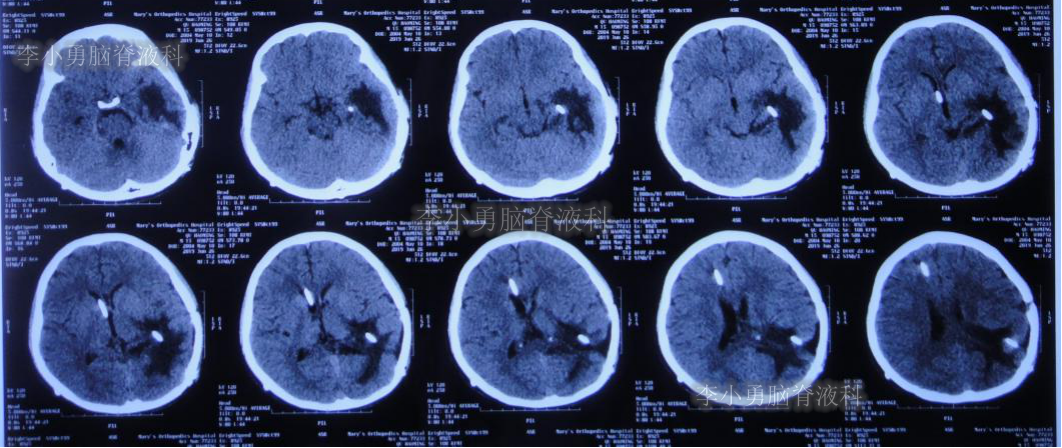

闭管40天后即2019年9月9日复查头颅CT(图-23):脑室仍无扩大。给予拔除右侧脑室外引流管并行左侧颞角-腹腔分流术。

图-23:2019年9月9日头颅CT:拔除右侧脑室外引流管后复查

2019年9月19日(李小勇脑脊液科治4个半月)出院,出院时:意识清楚,能自己走路基本正常,能自己吃饭,日常生活自理,但遗留动脉瘤切除术后记忆力差(图-24)。

图-24:2019年9月19日出院时